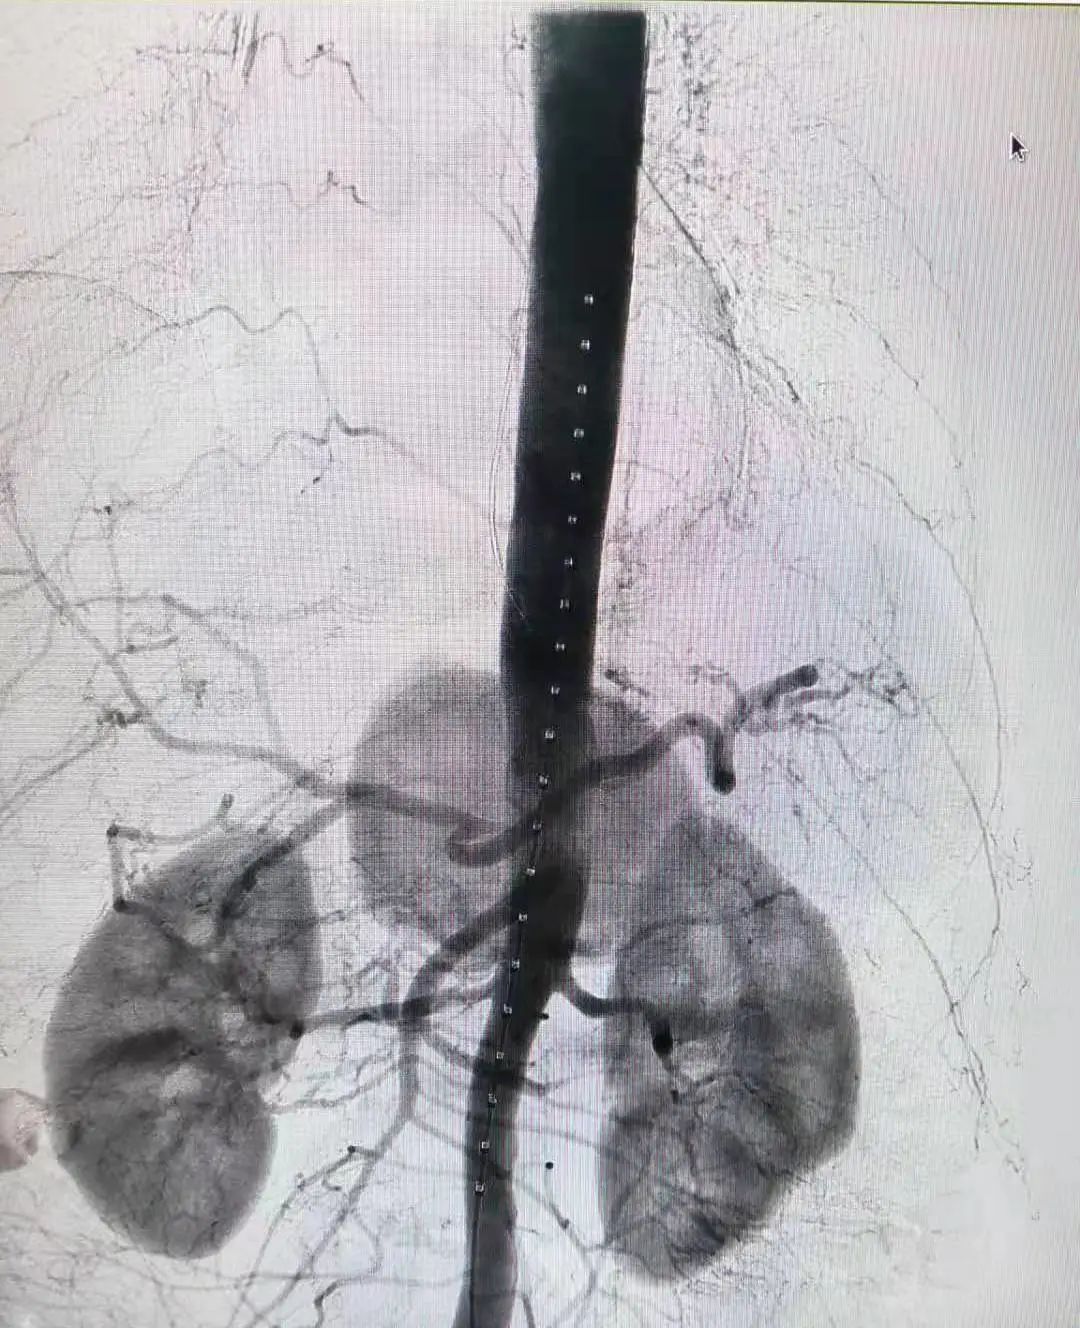

副院长王兵教授带领血管外科崔文军主任、司江涛主管医师及王广华大夫向这一高难度手术发起了挑战。手术团队参考「八爪鱼技术」,将 3 条短的覆膜小支架插入并缝合进传统「人」字型分叉覆膜大支架短腿分支内,成功制备成主体覆膜大支架(图 2)。

图 2